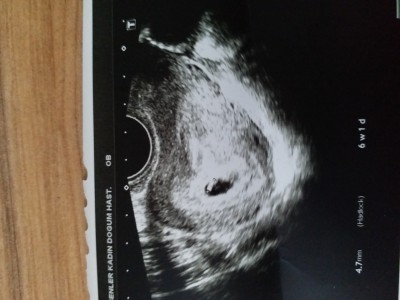

Doktor bugun keseyi gordu ama bebegi ultrasonda goremedi .alttan muayene etti cok kucuk bısey gozukuyo 10 gun sonra yine gel dedi . siz bisey gorebiliyo musunz

Gebelik haftası 6. Hafta

kese siyah alan olması  lazim kirmizi alanla işaretli alan bebis onunda yukari doğru kısımdaki koyulu acıklı olan olabilir yani daha bir mercimek tanesi kadar :)

Evet benimde 9 haftalık olacak o siyahligin içinde gördüğün sey bebek aslinda ama tabi o da tam bebek değil onunda kucuk bir kısmı bebek :) ama daha cok kucuk şuan bende ilk fasulye filan demiştim ama o da değilmiş mercimek tanesi oluyorlar o zamanlar :)